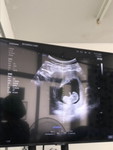

40weekแล้วววว

กรณีที่ 40weekแล้วเเต่ยังไม่น้ำมีเดิน หรือมูกออกมาคุณหมอจะฉีดยาเร่งคลอดให้มั้ยคะ พอดีอยากคลอดธรรมชาติค่ะ🥹